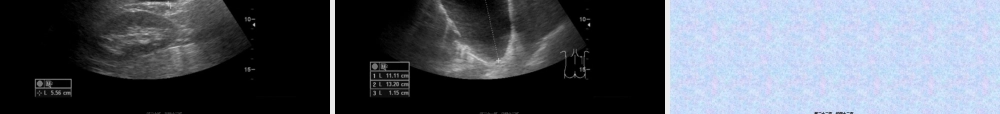

(fùbù)第一页,共四十二页。第一页,共四十二页。常用(chánɡyònɡ)概念•超声人耳可以接受的频率(pínlǜ)范围16~20000Hz,高于20000Hz者称为超声,常用的诊断超声频率2.5~7.5MHz。超声在人体内传播速度平均为1540m/s。•超声诊断利用超声波在人体组织内传播过程中,经过声反射等原理,将获得的信息加以分析综合,借以探索体内器官生理和病理变化,由此来判断疾病的一种诊断方法。第二页,共四十二页。第二页,共四十二页。超声诊断仪分类(fēnlèi)•A型:幅度(fúdù)调制型•B型:辉度调制型•M型:超声心动图•D型:ColorDopplerFlowImaging•三维超声第三页,共四十二页。第三页,共四十二页。回声描述(miáoshù)分类•无回声介质(jièzhì)均匀,内无界面反射,透声良好,主要用于含液性器官或病变。•低回声介质结构细,内部少界面反射,多见于实质而均匀的器官和病变。•强回声表明界面反射复杂,声阻大,见于含气体和钙盐的器官和病变。•声影表明界面声阻极大,使声能大量反射,形成强回声光团,其后方形成纵向条状暗带第四页,共四十二页。第四页,共四十二页。临床(línchuánɡ)应用范围颅脑、眼部、甲状腺、乳腺、心脏、肝脏、胆道、胰腺、脾、腹膜(fùmó)后、阑尾、泌尿系、妇科、产科、软组织、关节、血管等等第五页,共四十二页。第五页,共四十二页。第六页,共四十二页。第六页,共四十二页。介入性超声介入超声也称作超声引导靶向诊疗技术(InterventionalUltrasound),其主要(zhǔyào)特点是在实时超声的监视或引导下,完成各种穿刺活检、造影以及抽吸、插管、注药、消融等操作,是现代超声医学的主要(zhǔyào)分支,也是目前微创手术的方向之一。第七页,共四十二页。第七页,共四十二页。第八页,共四十二页。第八页,共四十二页。BB超下显示打开超下显示打开(dǎkāi)(dǎkāi)的电极针的电极针治疗结束治疗结束(jiéshù)(jiéshù)后显示后显示治疗区域的状态治疗区域的状态超声引导超声引导(yǐndǎo)(yǐndǎo)下肝肿瘤射频消融下肝肿瘤射频消融第九页,共四十二页。第九页,共四十二页。射频术后即刻增强射频术后即刻增强CTCT显示低密度灶,显示低密度灶,边界边界(biānjiè)(biānjiè)清楚,密度均匀,无强化清楚,密度均匀,无强化第十页,共四十二页。第十页,共四十二页。治疗治疗(zhìliáo)(zhìliáo)前前治疗治疗(zhìliáo)(zhìliáo)后后超声引导下肝肿瘤酒精超声引导下肝肿瘤酒精(jiǔjīng)(...